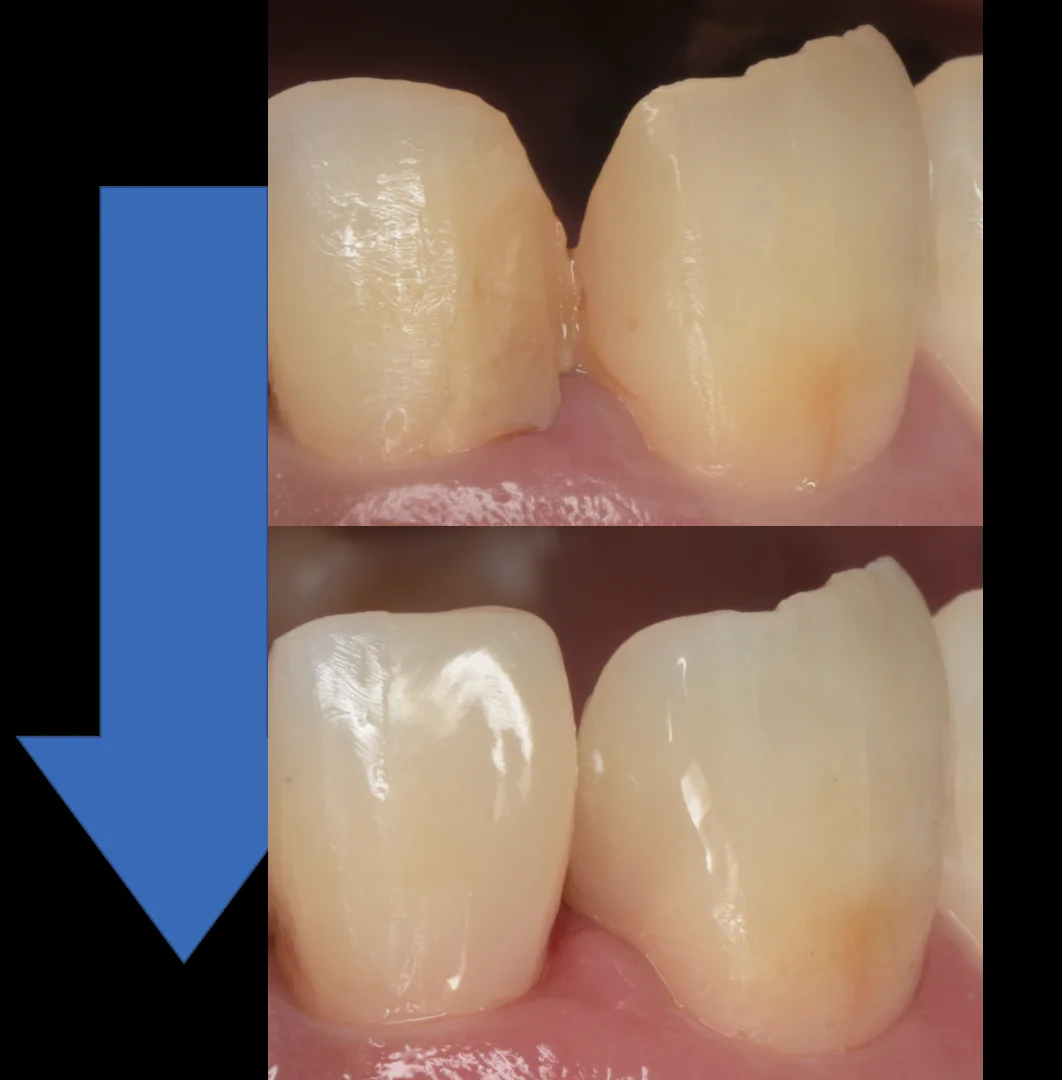

術前術後の比較がこちらですね。

歯茎からの立ち上がりを見てもらうとどれだけ適合が悪かったかがわかるかと思います。

歯茎を無理やり押し退けたので、元に戻るまでは1週間くらいはかかってしまいますが、適合はしっかりと合わせているので炎症のない綺麗な歯茎になってくれるかと思います。